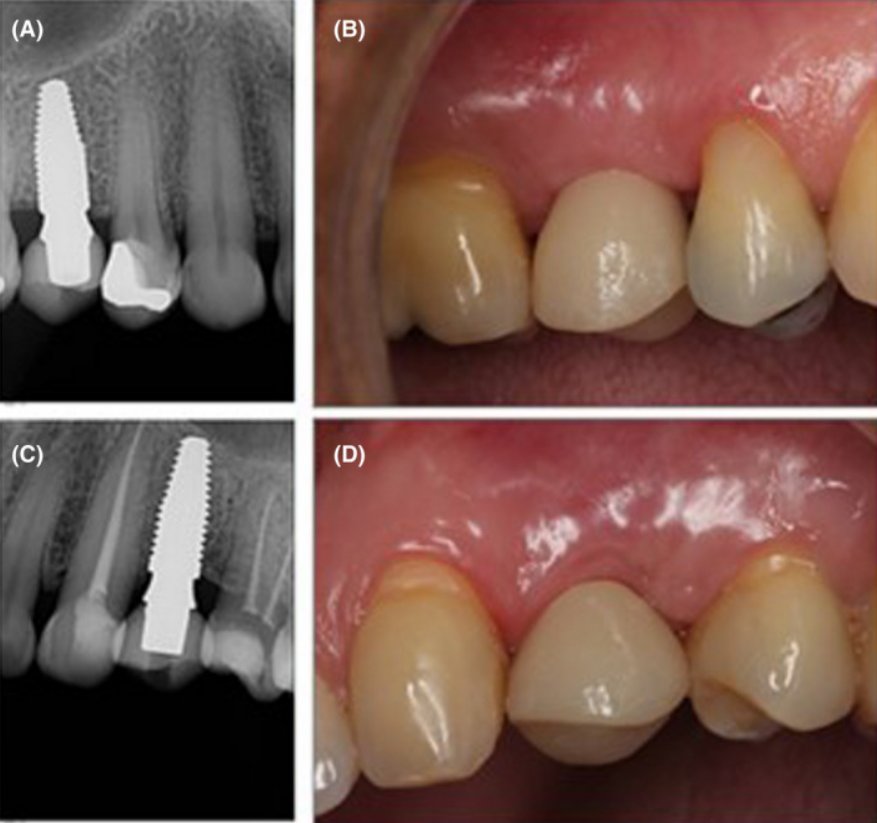

Клінічний випадок: заміщення втрачених 15 і 24 зубів за допомогою імплантатів Neodent Zirconia з подальшим протезуванням.

Процес встановлення імплантатів та відповідні прицільні знімки.

Встановлені імплантати з негайно виготовленими тимчасовими конструкціями.